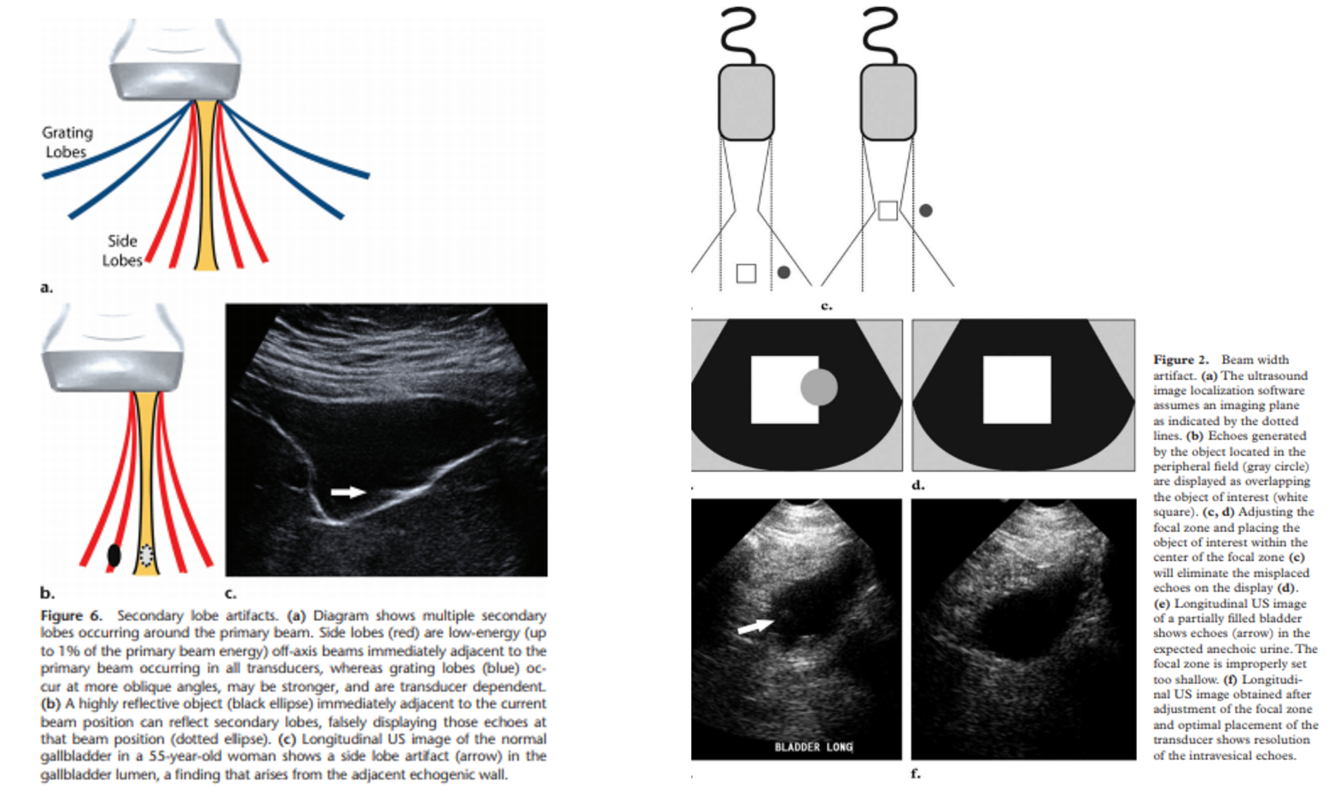

US beam related artifacts:

do side lobe artifacts happen more with linear or curved US arrays?

linear arrays

how do you decrease beam width artifact?